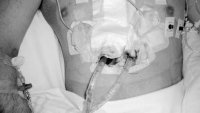

Alfentanil ved fjerning av retrosternale toraksdren

Studien viste høy grad av pasienttilfredshet og få bivirkninger ved bruk av det smertestillende middelet alfentanil ved fjerning av retrosternale toraksdren.

Smerter ved fjerning av retrosternale thoraxdren

Studien viser at dokumentasjon av smerte- og smertebehandling ved fjerning av retrosternale thoraxdren ofte er mangelfull og tilfeldig.